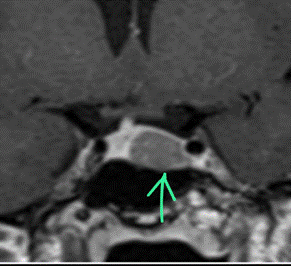

A dynamic contrast-enhanced MRI study highlighted the pituitary

microadenoma (Fig 1). Inferior petrosal sinus sampling confirmed an ACTH-

secreting pituitary adenoma on the left side (peripheral ACTH - 11.6pg/ml,

right IPS- 26.9, left IPS – 44).

Figure 1. Coronal section, T1 weighted post-contrast dynamic

sequence image of the pituitary fossa showing the tumour, a rounded region of

delayed enhancement (green arrow) compared to the rest of the gland.